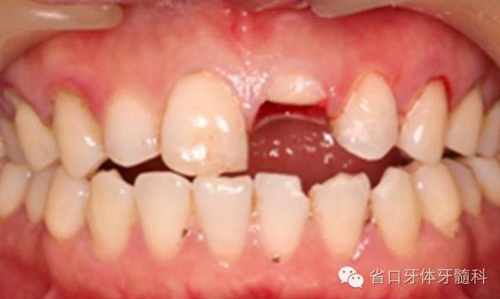

圖2. 術(shù)前口內(nèi)照片,21/冠折。

圖4. 拔除斷冠后的唇面照片